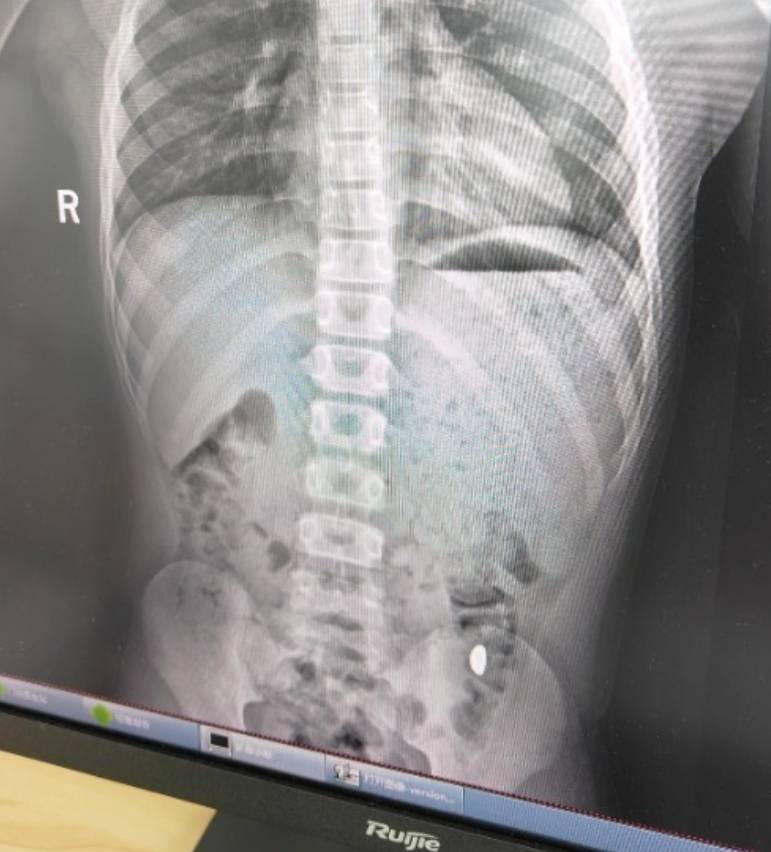

右下加亮点为金豆商业银行理财。